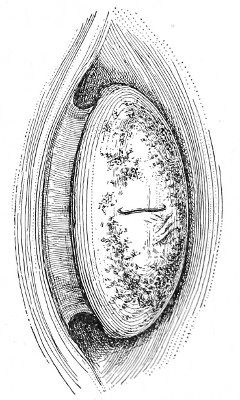

Cysts of the Vulvo-vaginal Glands.—Cysts may 41 occur in the duct of the vulvo-vaginal gland or in the gland itself. Cysts of the duct are small—about the size of a chestnut. They are situated superficially, lying immediately under the mucous membrane of the vagina at the base of the labium minus.

Fig. 18.—Cyst of the right vulvo-vaginal gland (Hirst).

Cysts of the gland may be unilocular if formed at the expense of a single lobule of the gland, or multilocular if several lobules enter into their formation. These cysts may attain the size of the fetal head (Fig. 18).

Cysts of the gland or of the duct are formed by retention of the cyst-contents. The retention is due to occlusion of the duct, usually the result of inflammation. In some cases the duct remains pervious, and the retention is due to the altered character of the secretion of the gland, which becomes too viscous to pass, except under unusual pressure, along the duct.

These cysts contain clear yellow or chocolate-colored 42 fluid. The diagnosis of cyst of the vulvo-vaginal gland is usually not difficult. If we are in doubt in regard to the fluid character of the tumor, this may be determined with the exploring-needle.

Inguinal hernia, hydrocele of the canal of Nuck, cysts of the round ligament, and sacculated cysts of old hernial sacs may be mistaken for cysts of the vulvo-vaginal glands. In such cases, however, the tumor lies more in the upper and outer part of the labium majus, and extends to, and may be connected with, the external inguinal ring.

Cysts of the vulvo-vaginal glands should be treated by free incision and packing, or by extirpation. If the sac is emptied by the aspirator or by a small incision, it will refill. The best method is to extirpate the cyst. In case there has been no inflammatory action binding the cyst to surrounding structures, extirpation without rupture is easy. If rupture occurs, the cyst-wall may be dissected off with the knife or removed with the curved scissors. The wound may be immediately closed with deep and superficial sutures.